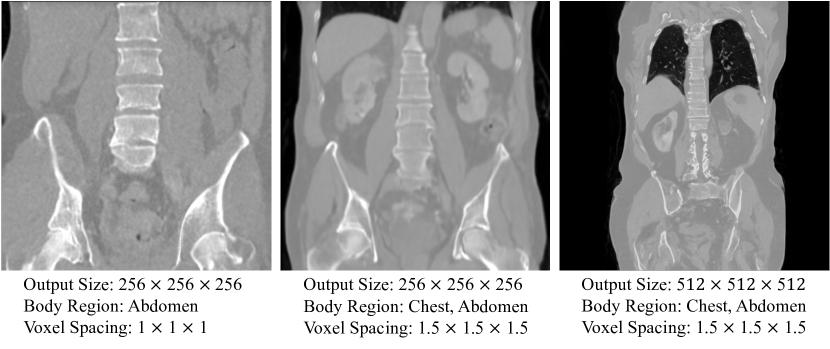

- flexible dimension의 압축된 latent space에서 작동, body region 및 voxel spacing을 conditional input으로 통합

- Body region : $i_{top}$, $i_{bottom}$ (촬영할 영역을 나타내는 one-hot vector)으로 작업할 CT 영역을 나타냄

- Voxel spacing : $s$ (voxel의 크기 3차원 vector)

- $c_p=\left\{ i_{top}, \, i_{bottom}, \, s\right\}$

- $\epsilon_{\theta}$는 전 training process에서 dimension이 달라지는 latent variable $z_t$ 학습, flexible volumetric dimension의 output 생성 가능

Response to primary conditions : Body regions, voxel spacing condition에 맞게 높은 flexibility와 control을 보여줌.